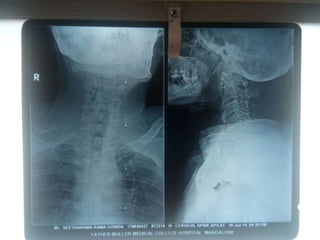

A case presentation was given by Mr. Ashik Dhakal and moderated by Mr. Sydney Roshan Rebello. Investigations were discussed for the case presented. The presentation concluded with thanks expressed.